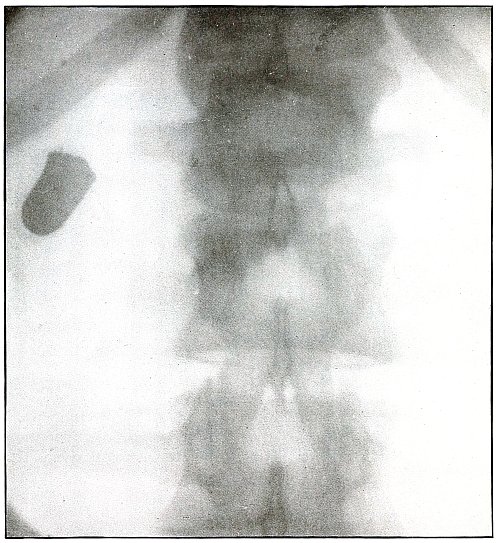

Rifle—Plate 46.

Gunshot Wound of the Pelvis, with Lodgment of the Missile in the Abdomen.

The course of the bullet was from behind forward, striking the crest of the ilium, on which it was deflected, and spattering off some lead fragments. The slight penetration indicates a velocity of extremely long range and a striking energy lessened by ricochet.

The irregular outline of the shadow of the projectile shows its deformity, and the blurred outline indicates intra-abdominal movement with respiration.

While the missile, as revealed by its shadow, is not a shrapnel ball, the distribution of lead particles is more suggestive of a shrapnel than of a rifle projectile, and the ballistic conditions are more characteristic of the former than of the latter.

There was no abdominal reaction; the invasion of the abdomen was revealed by the radiograph.

The treatment in such cases is noninterference unless subsequent developments furnish definite indications. [Pg 104]